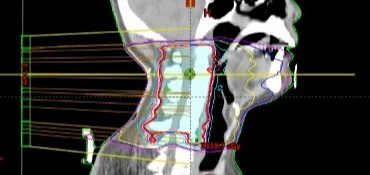

모의 치료 과정에서 CT 촬영이 끝나면, 컴퓨터를 이용해서 환자별 맞춤 치료 계획을 수립합니다. 이 치료 계획은 실제 치료로 전달되기 전에 실제 측정을 통해 정확한 양이 들어가는지를 검증한 후 치료를 진행합니다.

방사선 수술을 잘하기 위해서는 좋은 장비가 필요합니다. 간암에 방사선 치료에 유리한 장점을 가지고 있는 최신 장비뿐 아니라 숙련된 전문가가 필요합니다. 방사선 치료의 핵심은 정확한 곳에 적정량의 방사선을 조사하는 것이기 때문에 정확한 모의 평가가 매우 중요합니다.

환자의 정확한 호흡 패턴을 확인할 수 있는 4D CT 를 통해 호흡 시 움직이는 간 종양의 위치를 정확히 파악하는 것이 이 방사선 수술의 핵심이라고 할 수 있겠습니다. 정확한 방사선 조사는 부작용을 줄이고 주변 장기와 조직을 보존하는 길입니다.